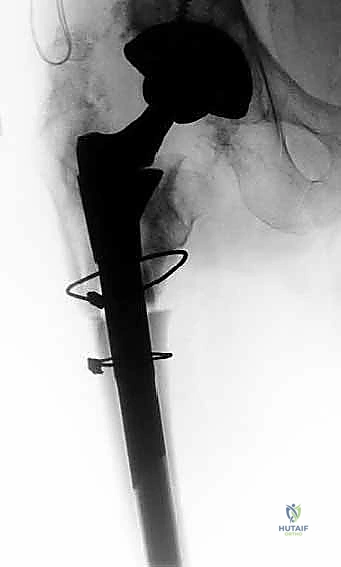

في حالات فقدان العظم الشديد أو صعوبة إزالة المفصل القديم، قد يلجأ الدكتور هطيف إلى تقنية متقدمة تُعرف بـ "قطع العظم المدوري الممتد" (Extended Trochanteric Osteotomy - ETO). يتم فيها شق جزء من عظم الفخذ طولياً لفتح القناة العظمية، مما يسهل إزالة المفصل القديم بأمان تام دون كسر العظم، ويوفر رؤية ممتازة لتحضير القناة للمفصل الجديد.

الخطوة الرابعة: زراعة الساق المخددة والتجربة

يتم إدخال الساق المخددة المصنوعة من التيتانيوم وتثبيتها بالطرق برفق حتى تنحشر بقوة في العظم السليم. إذا تم استخدام ساق معيارية (Modular)، يتم تركيب أجزاء تجريبية علوية لاختبار حركة المفصل، التأكد من عدم قابليته للخلع، وضبط طول الساقين ليكون متساوياً.

الخطوة الخامسة: الترقيع العظمي والإغلاق

إذا كانت هناك تجاويف عظمية كبيرة في الجزء العلوي من الفخذ، يقوم الدكتور هطيف بملئها بالطُعوم العظمية (Bone Grafts). إذا تم استخدام تقنية (ETO)، يتم إعادة إغلاق العظم المقطوع وتثبيته بأسلاك وكابلات معدنية قوية. أخيراً، يتم إصلاح العضلات والأنسجة الرخوة بدقة، وإغلاق الجرح تجميلياً.